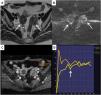

Aparte de valorar el comportamiento de las masas ováricas en secuencias anatómicas de alta resolución y de difusión, el sistema O-RADS RM utiliza curvas realizadas a partir del estudio dinámico con contraste que valoran la intensidad de señal-tiempo (CIT). Con estas curvas se compara el comportamiento de la captación de contraste del tejido sólido de la masa ovárica con la captación del miometrio, obteniendo 3 tipos de curvas que nos ayudan a estratificar el riesgo de malignidad. En la figura 1 se ejemplifican los 3 tipos de CIT y su correlación con la benignidad y malignidad de las masas ováricas.

Ejemplos de curvas intensidad-contraste (CIT) utilizadas en la clasificación O-RADS RM. A) La curva tipo 1 o de bajo riesgo muestra un aumento gradual de la curva sin aceleración inicial (flecha). Se asocia a bajo riesgo de malignidad. Estas masas no requieren cirugía oncológica. B) La curva tipo 2 o de riesgo intermedio (flecha) muestra una aceleración inicial menor que la del miometrio (curva amarilla en los 3 gráficos). Es típica de masas ováricas borderline, que, a efectos prácticos, deben ser intervenidas en centros oncológicos por su incierto potencial maligno. C) La curva tipo 3 o de alto riesgo (flecha) muestra una aceleración inicial igual o mayor que la del miometrio. Esta curva es característica de las masas ováricas malignas.